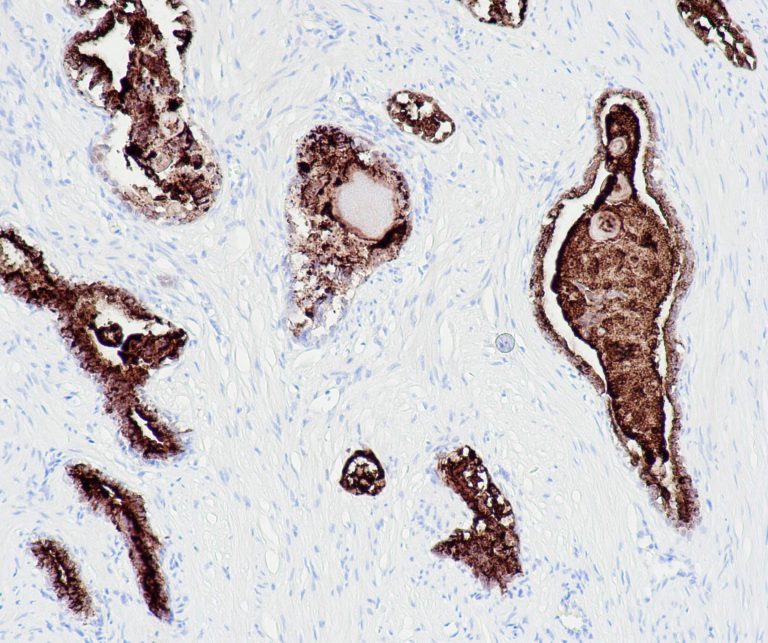

Breast Pathology

Gynecological Pathology

General Marker